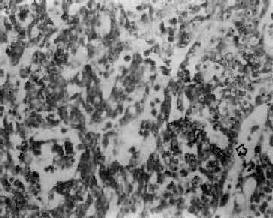

(4)未分化癌:癌细胞小而泡浆少,呈圆形或梭形,核圆形或卵圆形、浓染,细胞呈弥漫浸润,无明显癌巢形成。有时,癌组织主由短梭形细胞组成,颇似燕麦细胞癌(图9-7)。

图9-7 鼻咽未分化癌